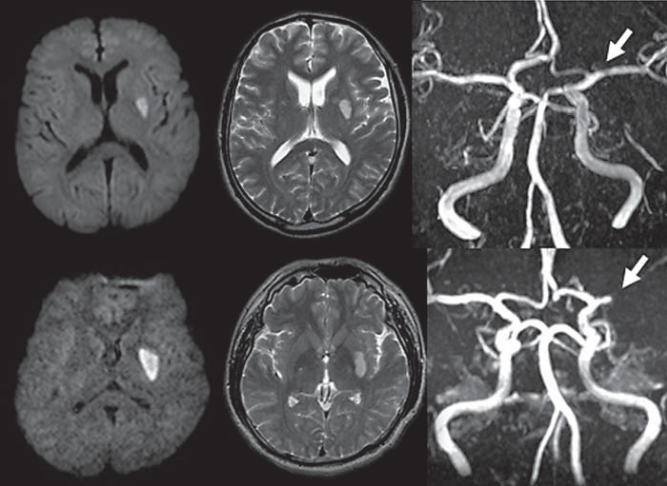

于永鹏:基于穿支动脉-神经组织单元论脑梗死模式分型_山东省威海市文登中心医院_ 于永鹏 迟相林 _365心血管网